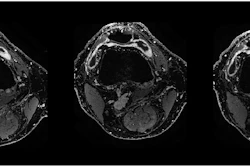

Peri-interventional digital subtraction angiography (DSA) of the descending genicular artery (DSA), a diagnostic procedure to view the inner surface of blood vessels, (green arrow) in a patient with symptomatic knee osteoarthritis of the right leg. On the left, the pre-interventional image with a clearly visible hyperemic blush (red box). On the right, the post-interventional DSA after embolization with Imepenem-Cilastatin. A completely eliminated blush is observed while preserving skin collaterals (orange arrows). Image courtesy of the RSNA.